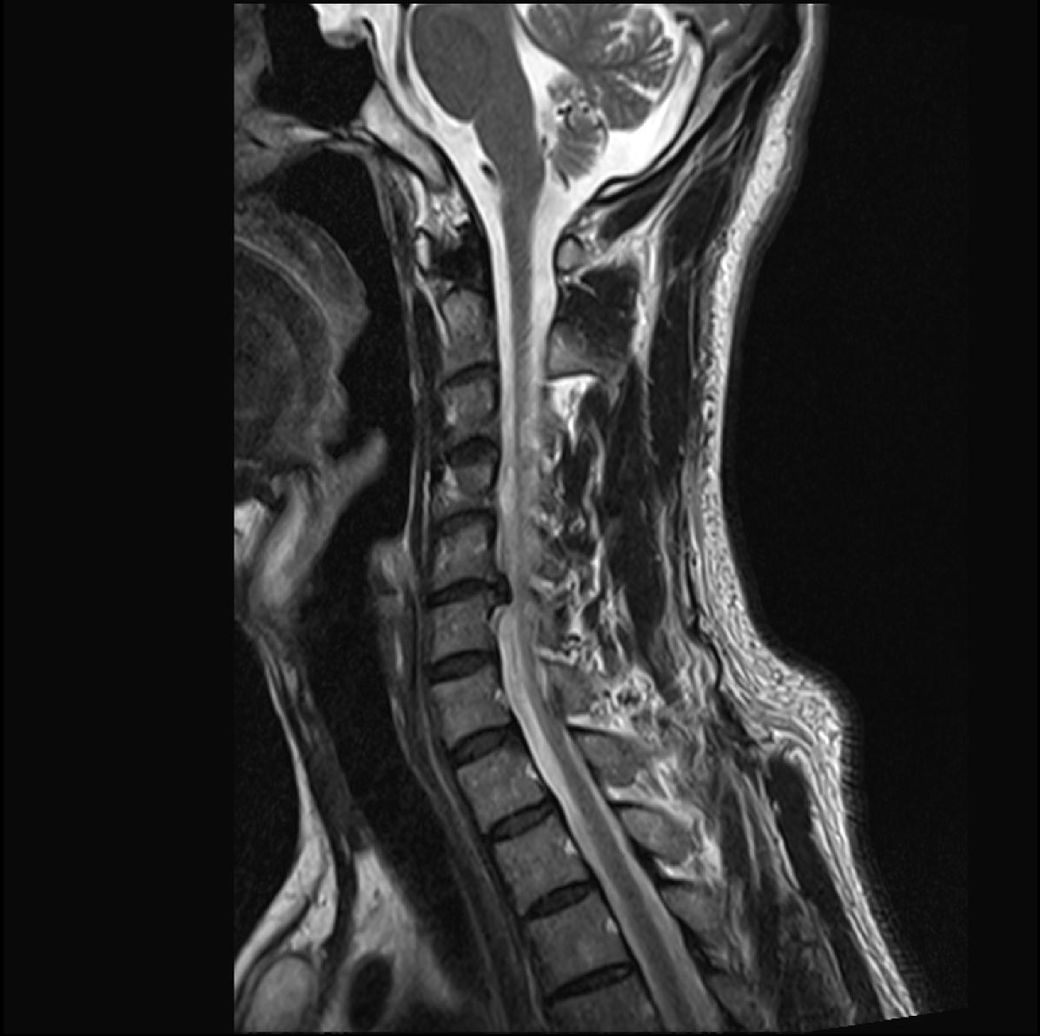

목 디스크 수술(시술)이 필요한 정도 인가요?

목이랑 왼쪽 어깨가 찌릿찌릿 아파서

mri를 찍었는데, 병원에서 목디스크라고 시술을 하자고 하는데,

보존 치료가 어려운 상황인가요?>